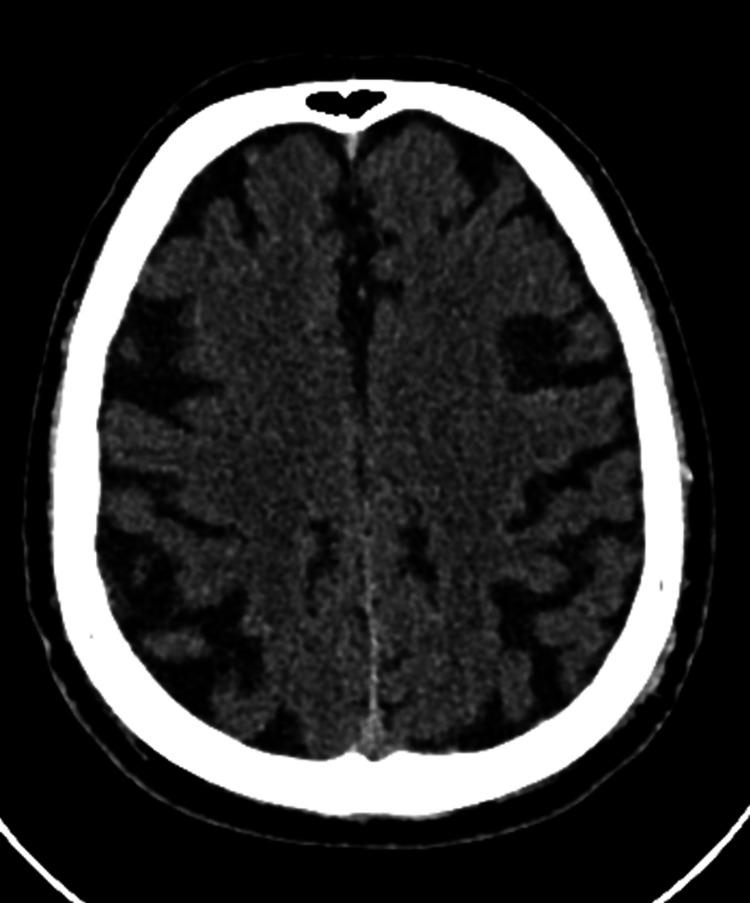

Hashimoto's encephalopathy (HE) is a rare autoimmune disorder, typically associated with Hashimoto's thyroiditis, and often presents with rapidly progressive cognitive impairment, psychiatric symptoms, and neurological deficits. Since the first case reported, there have been relatively few reports of HE cases, and it remains rare in Central America. A 59-year-old male patient with a past medical history of hypertension (HTN) and type 2 diabetes mellitus (DM2) was hospitalized due to a one-month history of rapidly progressive cognitive impairment associated with behavioral changes and episodes of amnesia. It was not associated with motor or sensory deficits, seizures, or movement disorders. Given this presentation, alongside normal head CT findings and mild age-related brain atrophy on MRI, the initial diagnosis posed a challenge. Further investigations, including cerebrospinal fluid (CSF) analysis, autoimmune panels, and viral encephalitis testing, helped exclude other potential causes of encephalopathy. Notably, elevated anti-thyroid peroxidase (anti-TPO) and anti-thyroglobulin (anti-TG) antibodies were detected, strongly suggesting HE. The patient responded favorably to immunosuppressive treatment with intravenous methylprednisolone and subsequent oral prednisone, leading to significant cognitive improvement and recovery of function. This case highlights the importance of considering HE in the differential diagnosis of rapidly progressive cognitive decline, especially when routine standard investigations do not reveal an alternative cause.

桥本脑病(HE)是一种罕见的自身免疫性疾病,通常与桥本甲状腺炎相关,常表现为快速进展的认知障碍、精神症状和神经功能缺损。自首例病例报告以来,HE病例的报道相对较少,在中美洲地区仍然罕见。一名59岁男性患者,有高血压(HTN)和2型糖尿病(DM2)病史,因1个月来快速进展的认知障碍伴行为改变和失忆发作而住院。该症状与运动或感觉功能缺损、癫痫发作或运动障碍无关。鉴于此临床表现,以及头颅CT检查结果正常和MRI显示轻度与年龄相关的脑萎缩,初步诊断颇具挑战性。进一步检查,包括脑脊液(CSF)分析、自身免疫指标检测和病毒性脑炎检测,有助于排除其他潜在的脑病病因。值得注意的是,检测到抗甲状腺过氧化物酶(抗-TPO)和抗甲状腺球蛋白(抗-TG)抗体升高,强烈提示为HE。该患者对静脉注射甲泼尼龙及随后口服泼尼松的免疫抑制治疗反应良好,认知功能显著改善,功能得以恢复。本病例强调了在快速进展性认知衰退的鉴别诊断中考虑HE的重要性,尤其是在常规标准检查未发现其他病因时。